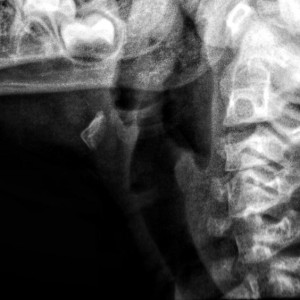

Отличительная черта синдрома Клиппеля-Фейля – короткая шея.